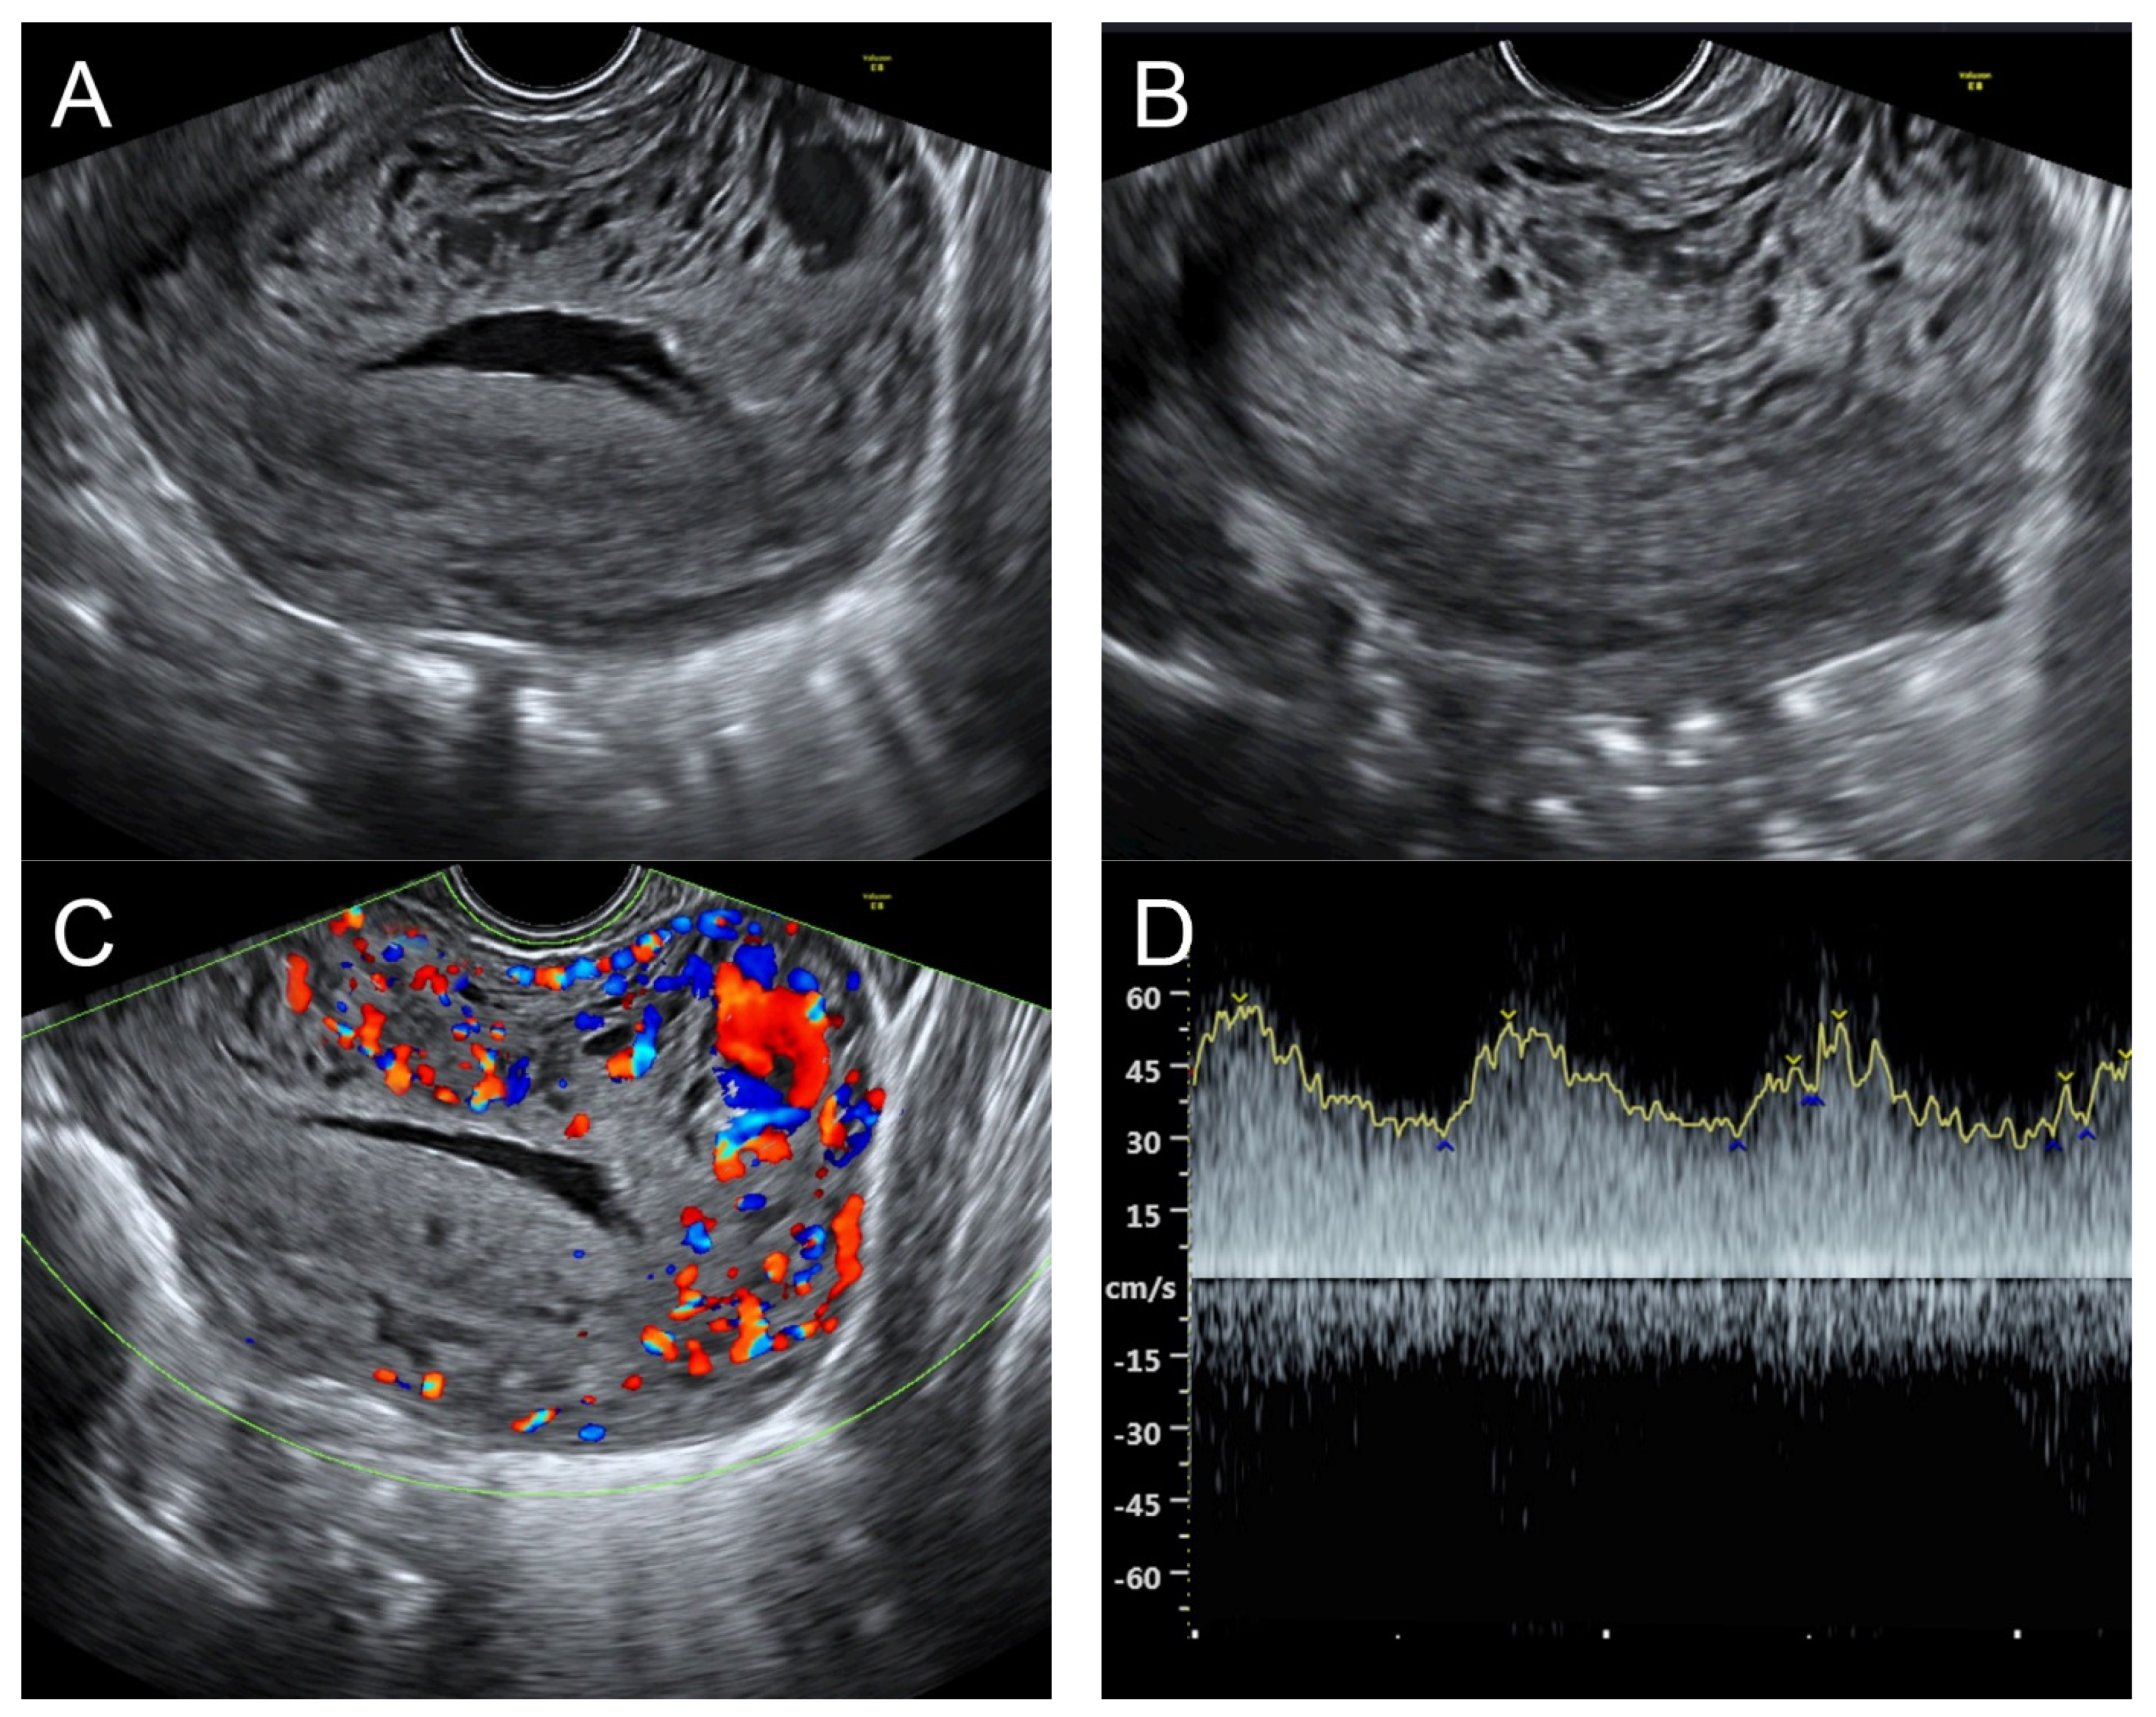

(A) Transvaginal ultrasound: sagittal scan of the uterus showed several dense small anechoic/hypoechoic tubular structures, mainly running to the endometrium, scattered throughout the anterior wall of the uterus; a thin endometrium; no other specific lesions of the uterus. There was anechoic fluid collection in the uterine cavity. (B) Cross-sectional scan of the fundus showed lesions with poorly defined outlines, containing several dense small anechoic/hypoechoic tubular structures, packed in the anterior wall. (C) Color flow mapping showed hyper-vascular areas in the myometrium, without well-defined lesion borders; multidirectional flow mainly localized at the anterior wall and the fundus. The main differential diagnosis was adenomyosis or gestational trophoblastic disease. (D) Spectral Doppler showed a high peak systolic velocity (~50 cm/s) with a low resistance index of 0.3. Note that in differentiating from adenomyosis, which sometime shows multiple minute anechoic or spongy-like areas but not lacunar lakes or tortuous vessels, adenomyosis is characterized by the absence of flow or minimal flow or by the presence of straight, scattered vessels traversing a hypertrophic myometrium [18,19], typically not containing a high flow peak systolic velocity, as seen in AMV, as mentioned earlier.